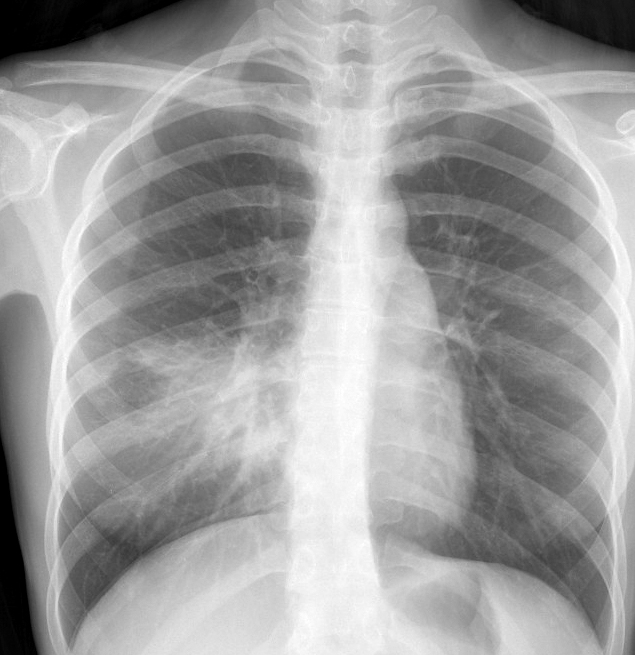

Gallery Pneumonia Case 4 RML pneum PA

Case 4 RML pneum PA